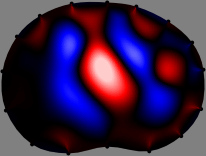

Figs. 3 and 4 compare the performance of the proposed FER method in (20) with the standard regularized least-squares method ((19) when is the identity matrix). The regularization parameter of the standard method was heuristically chosen for its best performance, and the parameter of the FER method was set to be one of three different values . The injection current was 1 mA at 100 kHz, and the frame rate was 9 frames per second. The reference frame at was obtained from the maximum expiration state. The measured data, , represent the voltage differences between each time and . The blue regions, which denote where conductivity decreased by inhaled air, increased during inspiration and decreased during expiration. The FER method with was clearly more robust than the standard method that produced more artifacts originated from the inversion process.

| Standard | |

||||||||||

| FER () | |